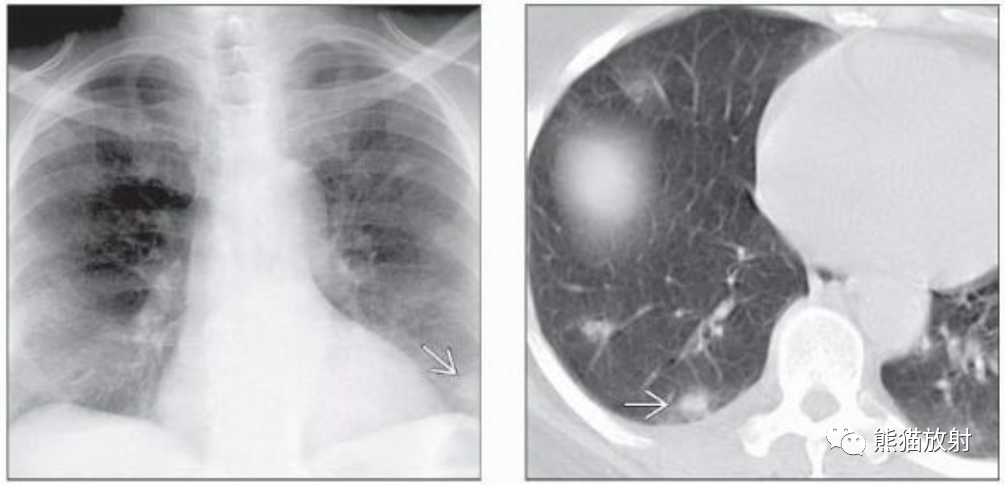

(左) 50岁男性,HIV感染并大咯血。胸片显示左肺上叶肿块,边缘不规则,其内局部透亮度增高,提示空气新月征。

(右) 同一患者,轴位CT显示厚壁空洞病变,中央见不均匀软组织密度灶,周围见磨玻璃影及小结节。术后诊断为侵袭性曲霉菌病。